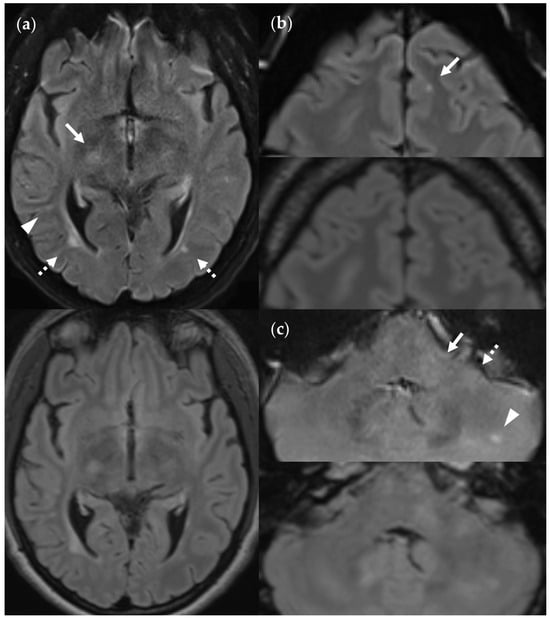

4.3. Limitations of the FLAIRUF Images

4.4. Considerations on Ratings for Lesion Conspicuity in FLAIRUF

4.5. Outcomes Correlated with Technical Features